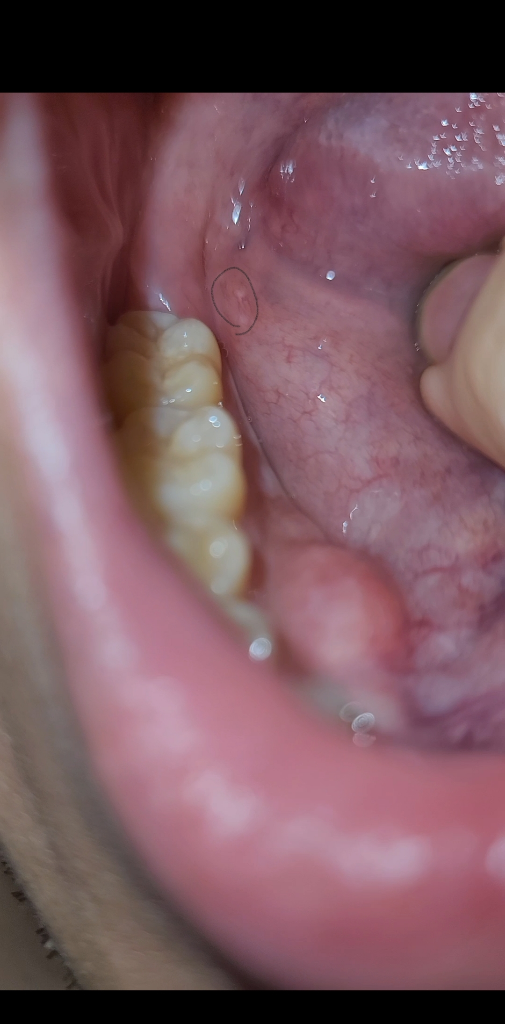

입에 뭐가 났는데 구강암일수도 있을까요?

위 사진처럼 구내염같은게 발견한지 12일째 안사라지는데 구강암일수도있나요??ㅠㅠ 술담배안하는데 너무 걱정이 됩니다ㅠㅠ

사진으로는 정확하게 확인하기가 힘들어 보입니다. 정확한 확인을 위해서는 치과에서 진료를 받아보는 것을 권유드립니다

구강암은 아닌거 같습니다. 저부위가 자극을 받아 수포처럼 생긴거 같으니 시간이 지나면 괜찮아 지실꺼에요

가능성은 높지 않습니다. 악성 병소의 경우 경결감(딱딱한 느낌), 자발출혈, 굉장히 지저분한 병소 양상 등이 특징적으로 나타납니다.

단순 구내염은 1~2주 정도면 증상 완화됩니다.

현재 사진상으로 구강암일 가능성은 낮습니다. 우선 소독용 헥사메딘 가글로 소독을 하고, 상태를 지켜보길 권하며, 만약 1달이 상 지속시에는 치과진료를 받길 권합니다.